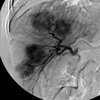

Arteriogram outlines the supply to the tumor (B)

as well as the hypervascular blush (C)